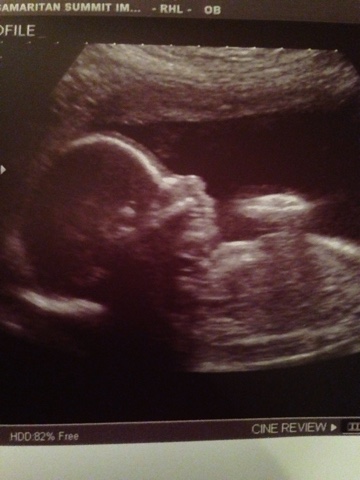

Baby Boy D - 21 Weeks

The second appointment today was an anatomy ultrasound.

Nik went with me to this appointment and he got to see Baby Boy D on the screen

as the technician looked at, took pictures of and measured our baby - for almost an hour!

It was so very cool to see our little baby boy!

We did get a few print outs - here is one: